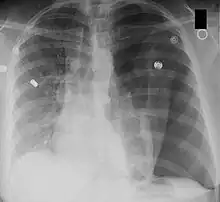

Left-sided tension pneumothorax. Note the area without lung markings which is air in the pleural space. Also note the tracheal and mediastinal shift from the patient's left to right.

Tension pneumothorax

A pneumothorax occurs when air collects in the pleural space around the lungs. Normally, this space has negative pressure to allow the lung to fill. Pressure increases as more air enters this space.[7] The lung collapses, impairing normal breathing. Surrounding structures may also shift. When severe enough to cause these shifts and hypotension, it is called a tension pneumothorax. This is life-threatening. The increased pressure inside the chest can compress the heart and lead to a collapse of the blood vessels that drain to the heart. The veins supplying the heart are compressed, in turn decreasing venous return.[7] With the heart unable to fill, cardiac output drops. Hypotension and shock ensue. If not rapidly treated, it can lead to cardiac arrest and death.[8]